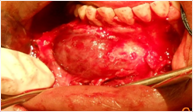

En el periodo peroperatorio se observó una sustancia líquida que rellenaba un saco de aspecto quístico en el proceso alveolar de la mandíbula derecha. Al examen macroscópico se observó un tejido blando pardo grisáceo que medía aproximadamente 4 cm de diámetro. El estudio macroscópico del corte de dicha pieza reveló un quiste con una pared fina de 0,1-0,5 mm de grosor con un diente canino impactado, el número 43 (fig.); en tanto, microscópicamente revelaba un espacio quístico delimitado por áreas sólidas del tumor y mostraba células poliédricas y espículas que formaban nidos, cordones y conductos.